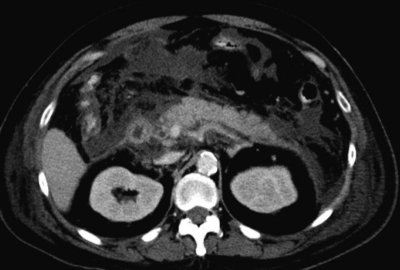

血液所見:赤血球 502 万、Hb 15.3 g/dL、Ht 45 %、白血球 12,700、血小板 26 万、PT-INR 1.1(基準 0.9〜1.1)。血液生化学所見:総ビリルビン 4.4 mg/dL、AST 370 U/L、ALT 177 U/L、LD 491U/L(基準 176〜353)、γ-GTP 337 U/L(基準 8〜50)、アミラーゼ 1,288 U/L(基準37〜160)、尿素窒素 23 mg/dL、クレアチニン 1.2 mg/dL。CRP 9.3 mg/dL。腹部造影CTを別に示す。